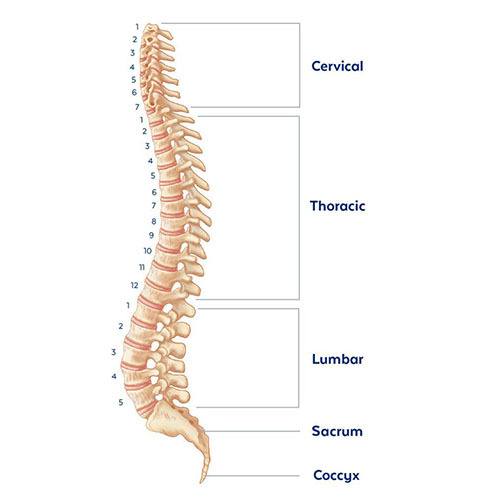

silikonsheet.blogg.se – Spine diagram

Bones-of-the-Spine-for-EMS – Handley Law

human spine anatomy diagram

Diagram Human Spine Name Description All Sections Vertebrae Vector …